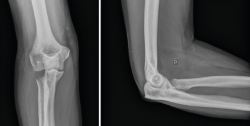

Las fracturas que afecten a menos de un tercio de la cabeza radial y que no produzcan bloqueo de la articulación podrían tratarse de igual modo que las de tipo I con buenos resultados a largo plazo. Inestabilidad y desplazamiento no son sinónimos. Incluso con un desplazamiento de más de 2 mm o con más de un fragmento, hay fracturas que siguen siendo estables gracias a que las estructuras periósticas están preservadas; por tanto, no son indicación absoluta de tratamiento quirúrgico (Figura 2)(11,12).

Figura 2. Ejemplo de fractura de Mason II tratada de forma conservadora. A: proyección anteroposterior (AP) aguda; B y C: AP y lateral a los 6 meses.